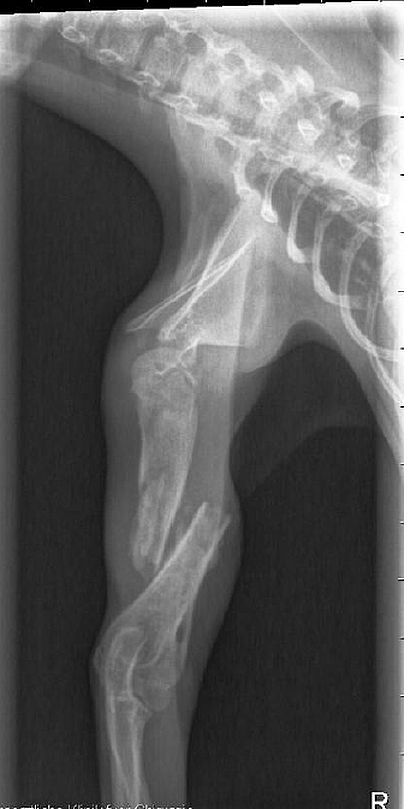

Das Beinchen sah nicht gut aus, daher wurde sie gleich in die Tierklinik gebracht. Dort stellte sich heraus, dass sie sich den Oberarm

gebrochen und sich dann auch noch der Nerv auf den Knochen aufgespießt hatte. Da der Bruch schon 8-10 Tage alt war, war dieser Nerv auch schon mit dem Knochen verwachsen.

Das Mädchen wurde sofort operiert und es ist auch alles soweit gut verlaufen und nun bekommt Izzy täglich Krankengymnastik, was sie vorbildlich mit macht und wir hoffen,